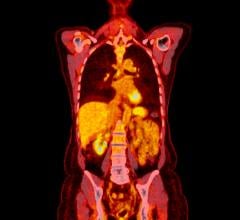

In the study, 65 chronic pain patients underwent 18F-FDG PET/MRI from head to foot. Maximum standardized uptake values and target-to-background ratios were measured using image analysis software. PET/MR images were evaluated by two radiologists to determine if increased 18F-FDG uptake occurred in the site of symptoms or in other areas of the body. Imaging results were then discussed with the referring physician, who determined whether a change in the pain management plan would follow.

Increased uptake of 18F-FDG in affected nerves and muscle was identified at the site of pain and other areas of the body in 58 out of 65 patients. This resulted in a mild modification of management plan (e.g., additional diagnostic test) for 16 patients and a significant modification for 36 patients (e.g., new invasive procedure suggested or ordered). In total, new management plans were implemented for 40 out of 65 patients, which had not been anticipated by the referring physician.